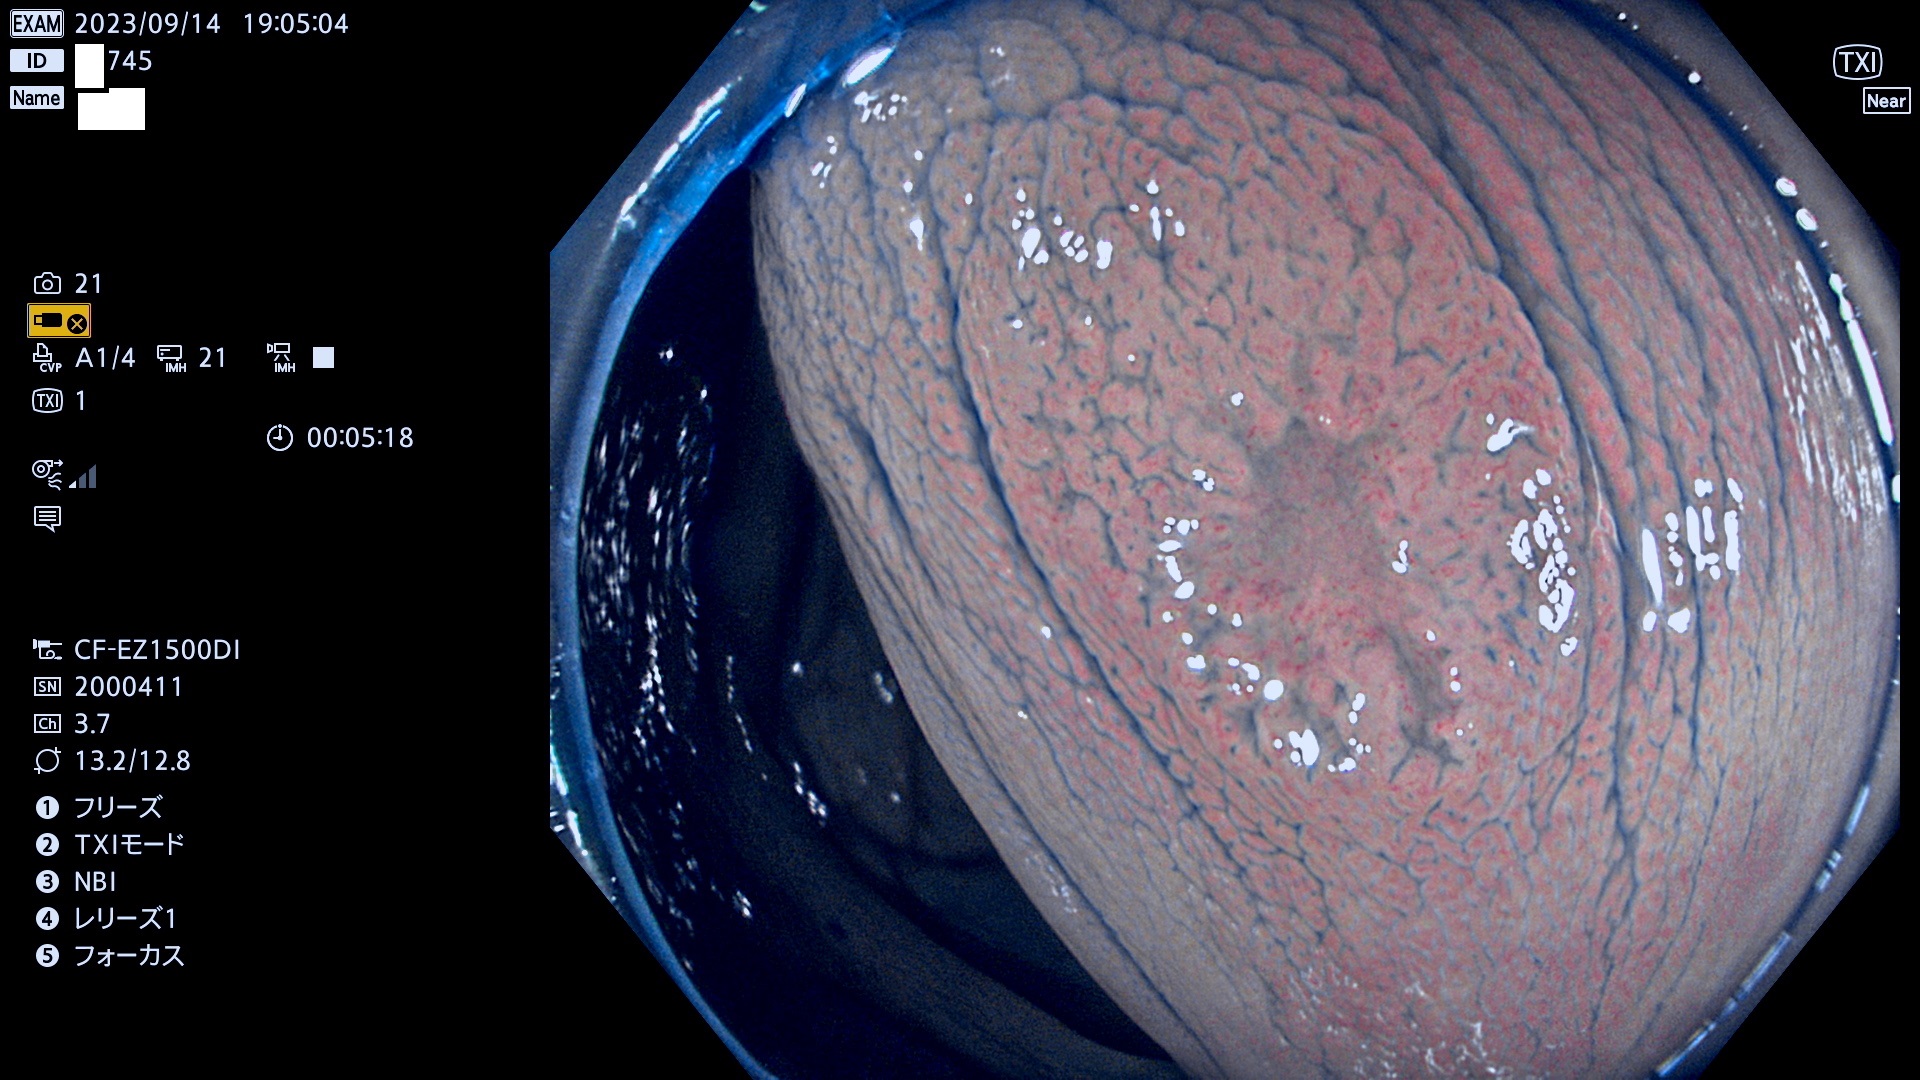

今週のUb、Uc型腺腫

表面型腺腫(Flat Adenoma)の中で、完全に平坦な物をUb、陥凹している物をUcと呼びます。平坦隆起型(Ua)よりも、発見が難しく危険な病変です。このタイプは「内視鏡後・大腸癌の重要犯人」であり、この発見率は「腺腫発見率」よりも、重要な意味があります。

毎週の検査(木・金・土・日)に発見されたUb、Uc型・腺腫を、その週の日曜の夜にUPし1週間、提示します。

抽出の対象期間 2023年9月14日(木)〜9月17(日)の4日間(48件の検査)7件